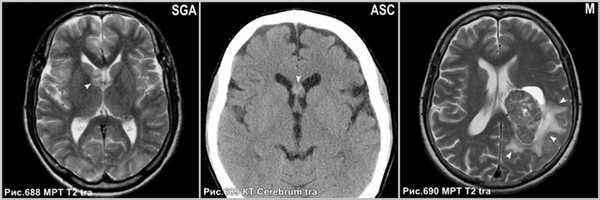

Субэпендимарная гигантоклеточная астроцитома (рис.688) встречается исключительно у пациентов с туберозным склерозом и интенсивно накапливают контраст.

Астроцитомы редко располагаются в желудочковой системе (рис.689).

Интравентрикулярные менингиомы (рис.690) имеют гомогенное контрастирование с определением чётких ровных контуров.

![central_neurocytoma_5]()

Субэпендимарная гигантоклеточная астроцитома с типичным расположением в области отверстия Монро (головка стрелки на рис.688). Астроцитома, растущая из прозрачной перегородки экзофитно в просвет правого и левого бокового желудочка (головка стрелки на рис.689). Внутрижелудочковая менингиома в центральном отделе левого бокового желудочка (звёздочка на рис.690), сопровождающаяся перифокальным вазогенным отёком прилежащего белого вещества перивентрикулярной зоны (головки стрелок на рис.690).